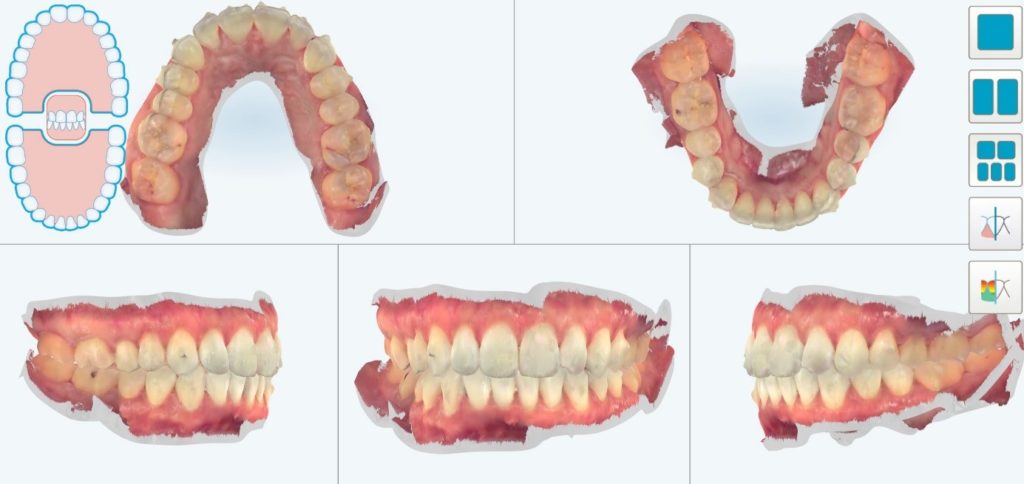

Au bout du port de celles-ci, nous avons constaté un défaut dans le positionnement des dents, probablement dû à la difficulté de certains mouvements de tipping et un manque d’alignement des milieux.

Il a été décidé de réaliser une série de finitions supplémentaires pour parfaire le résultat.

On peut constater ici :

• Une série de 8 aligneurs supplémentaires à changer toutes les semaines cette fois-ci

• Un ajout de 2 RIP au maxillaire pour le décalage des milieux

• Un ajout de 3 RIP à la mandibule pour le décalage des milieux

• Un nombre de taquets très inférieur au premier Clincheck, les mouvements à faire étant bien moins importants au final

La contention finale se fera par gouttières amovibles nocturnes bimaxillaires.